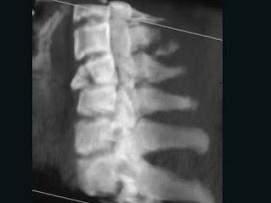

问题 男,68岁,从一两米高的平台坠落后颈部疼痛6小时,请结合影像学检查,选出最可能的诊断 ( )

选项 A、化脓性脊柱炎 B、强直性脊柱炎 C、椎体压缩性骨折 D、脊椎转移瘤 E、脊椎结核

答案 C